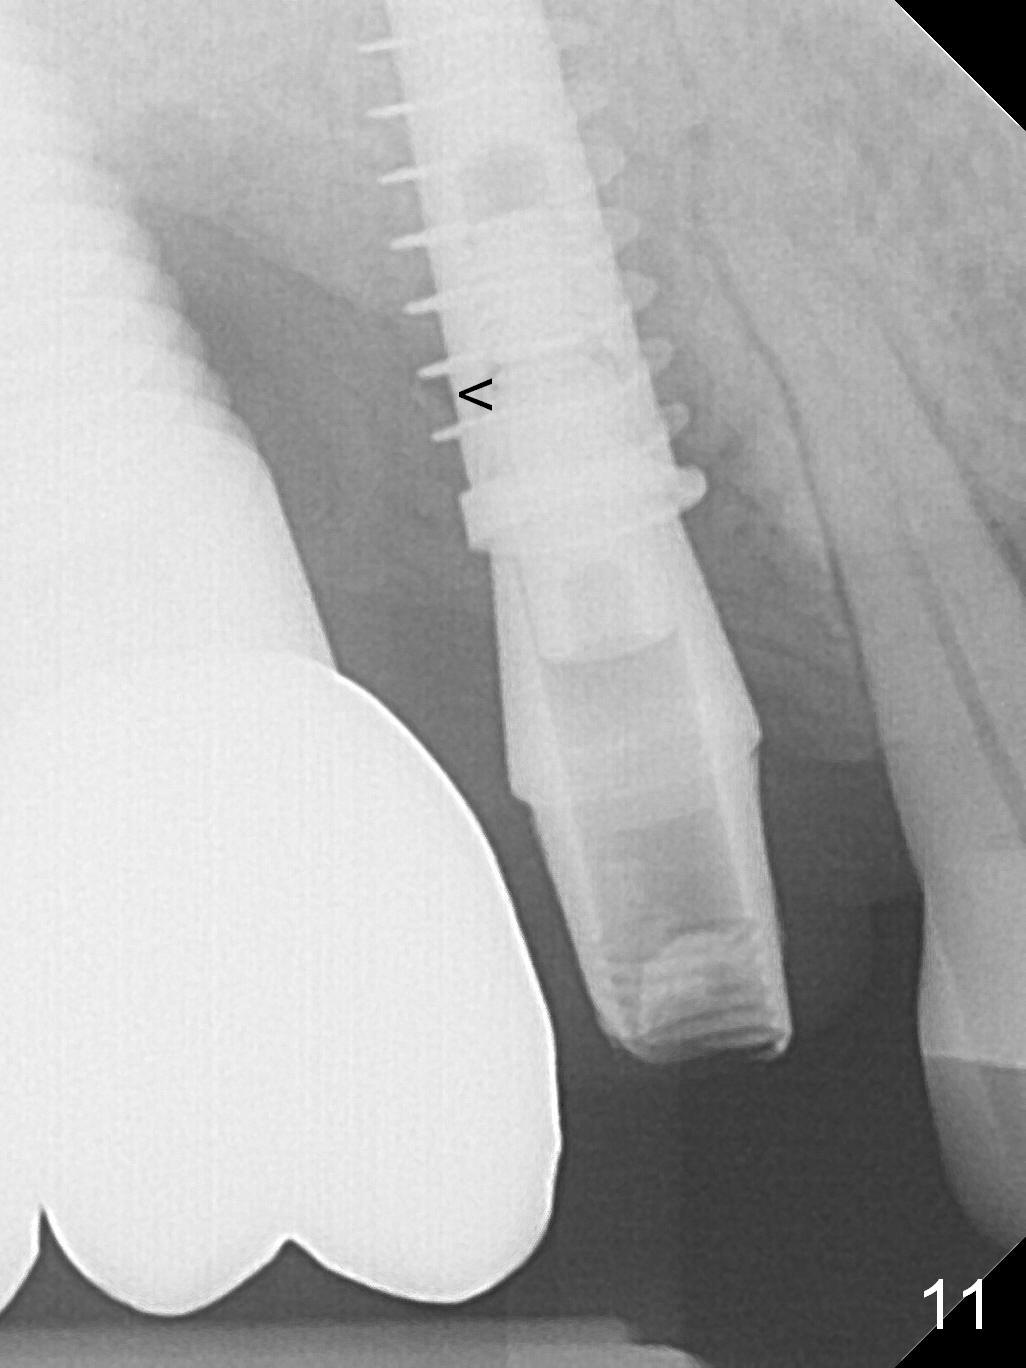

The distal papilla reforms buccally (Fig.8 *) and palatally (Fig.9) 4 months postop. It appears that the 4 mm cuff of the pair abutment (Fig.10 >) is apical to the mesial crest (*). The distal coronal implant threads seem to be covered by bone graft (Fig.11 <). Therefore pair abutments with 5 mm or more cuff are required in cases of the uneven bone. Implants have to be placed deep. CT taken 3 months post cementation (10 months postop) shows that the implant is placed in the middle of the alveolus without apparent thread exposure. CT taken 1 year and 8 months post cementation (Fig.13) shows that the implant is placed in the middle of the alveolus without apparent thread exposure, as compared to those at #2 and 3, which are placed buccal (B).